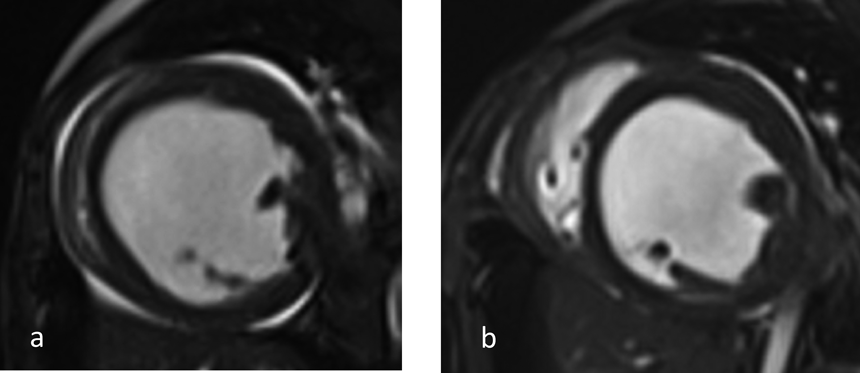

特発性拡張型心筋症に対し肺動脈絞扼術を施行した1乳児例Pulmonary Artery Banding in an Infant with Idiopathic Dilated Cardiomyopathy